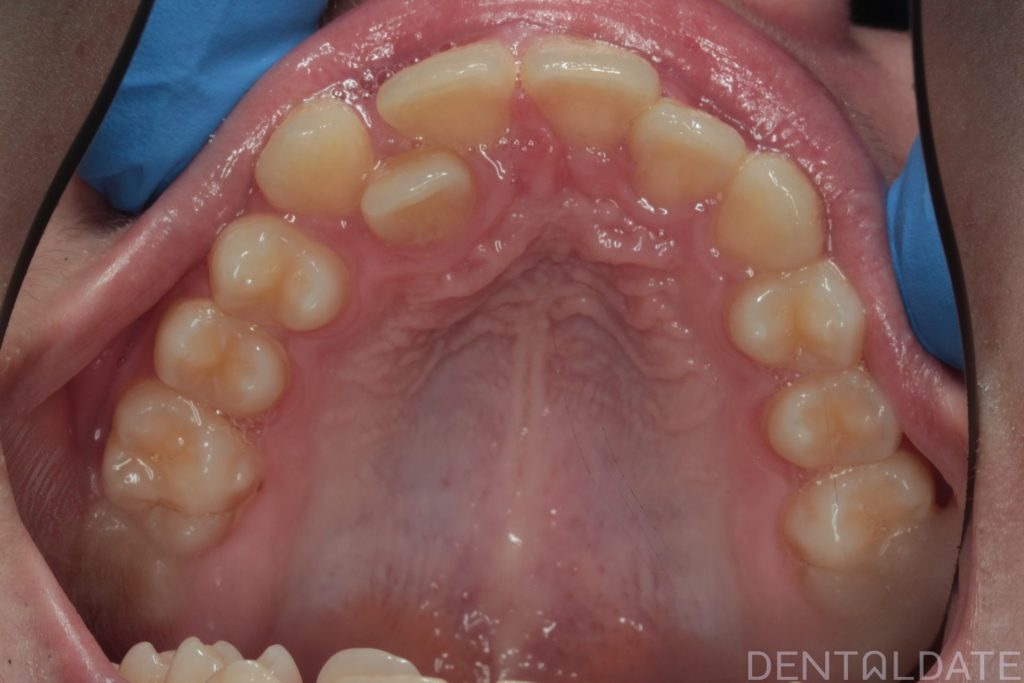

One tooth had erupted palatelly, with no space available for it in the dental arch.

The central aesthetic lines did not match, and the bite was incorrect.